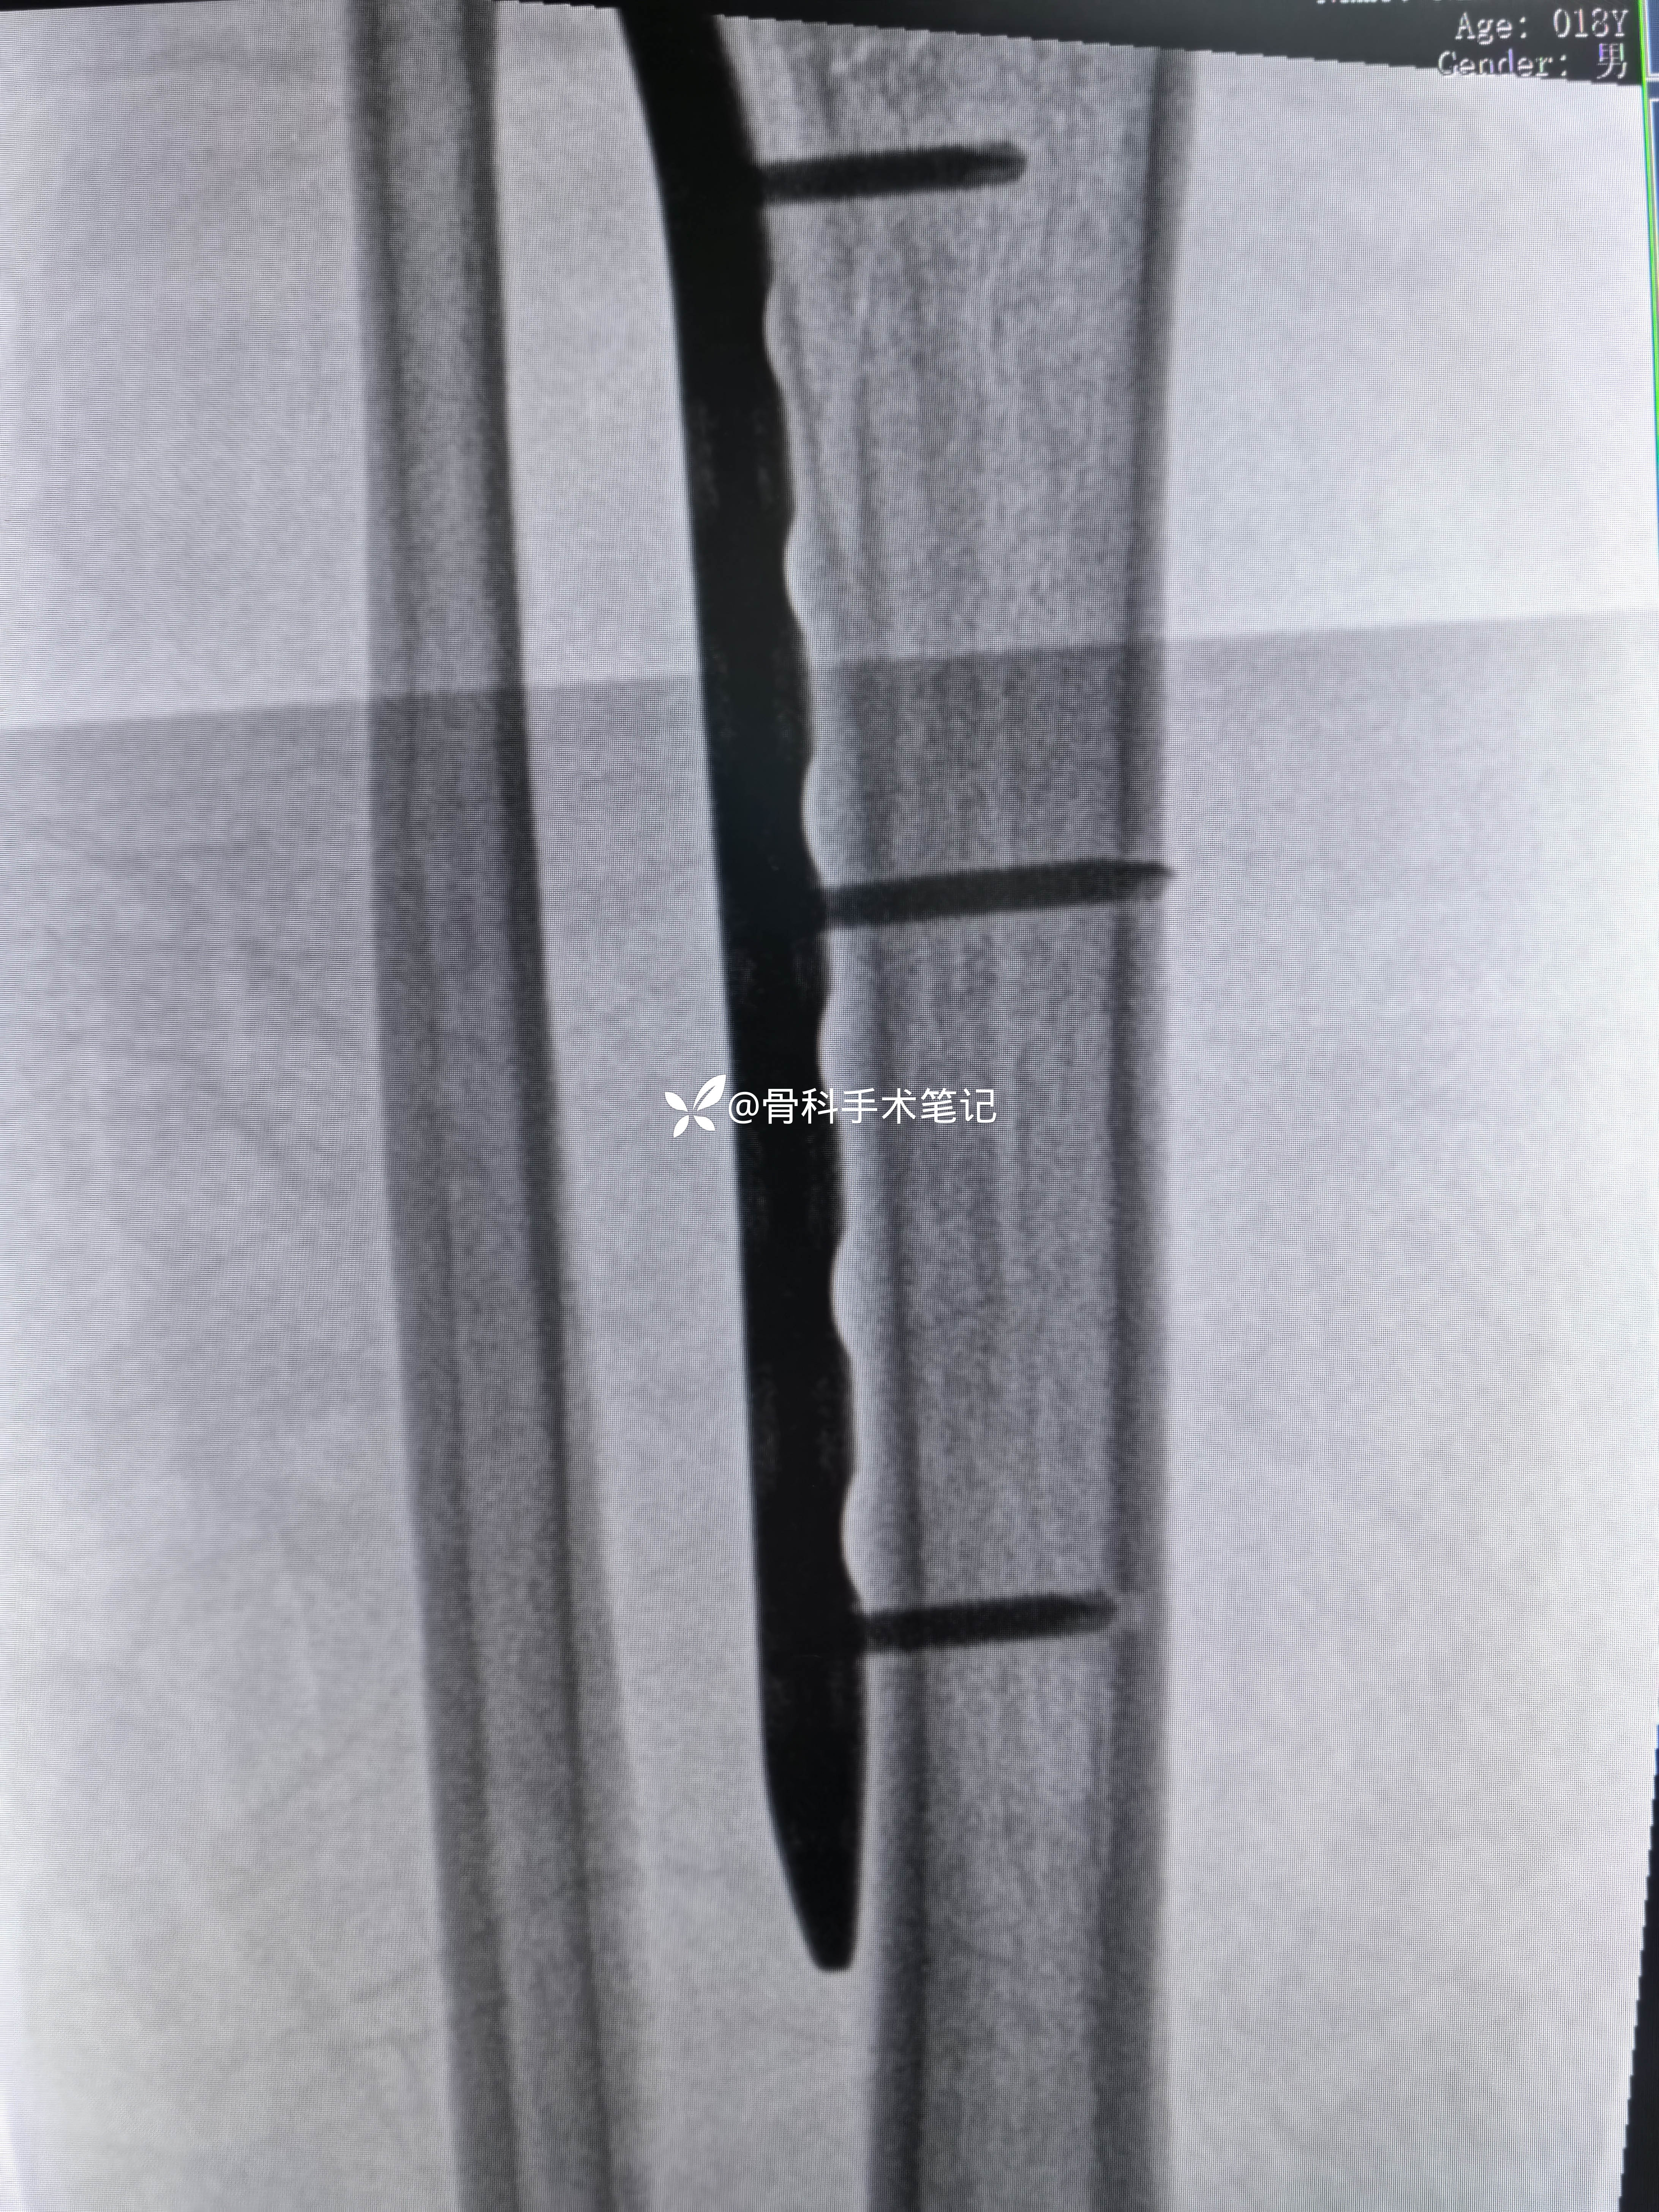

术后影像资料